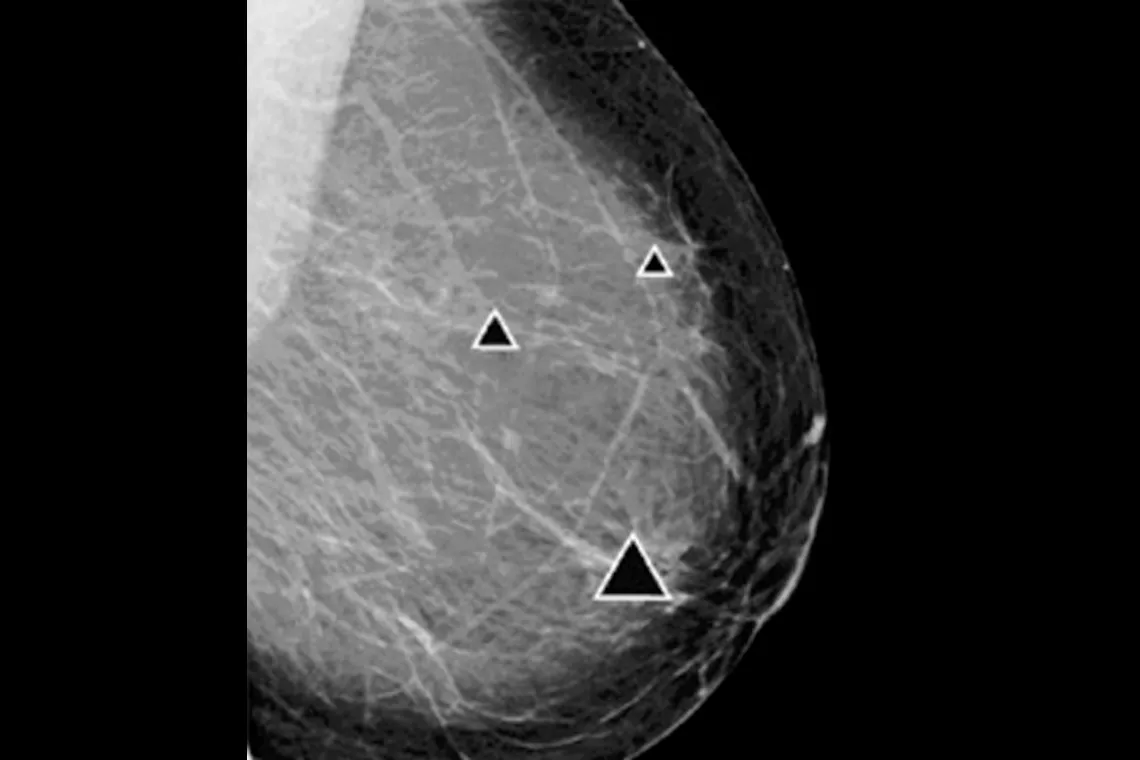

ImageChecker 2D CAD Technology searches digital mammograms for potential microcalcifications and masses, characteristics commonly associated with breast cancer.

• Regions-of-interest are highlighted for the radiologist’s attention

• Delivers highly sensitive results without excessive false-positive marks, streamlining case review2